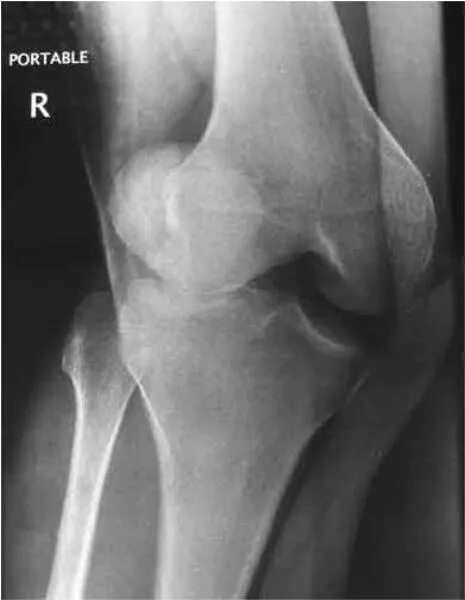

Вывих надколенника код мкб 10